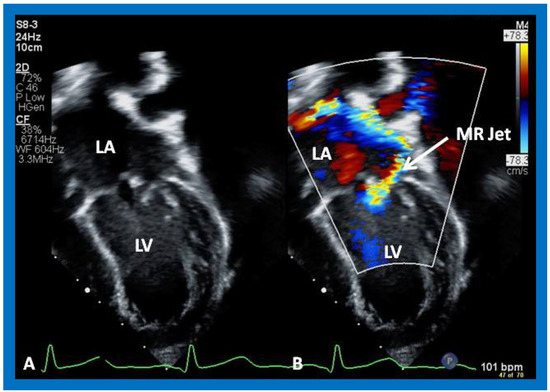

Figure 36. Selected video frames from apical four chamber view demonstrating dilated left atrium (LA) and left ventricle (LV) (A,B). Note the mitral insufficiency jet (MR Jet) in (B).